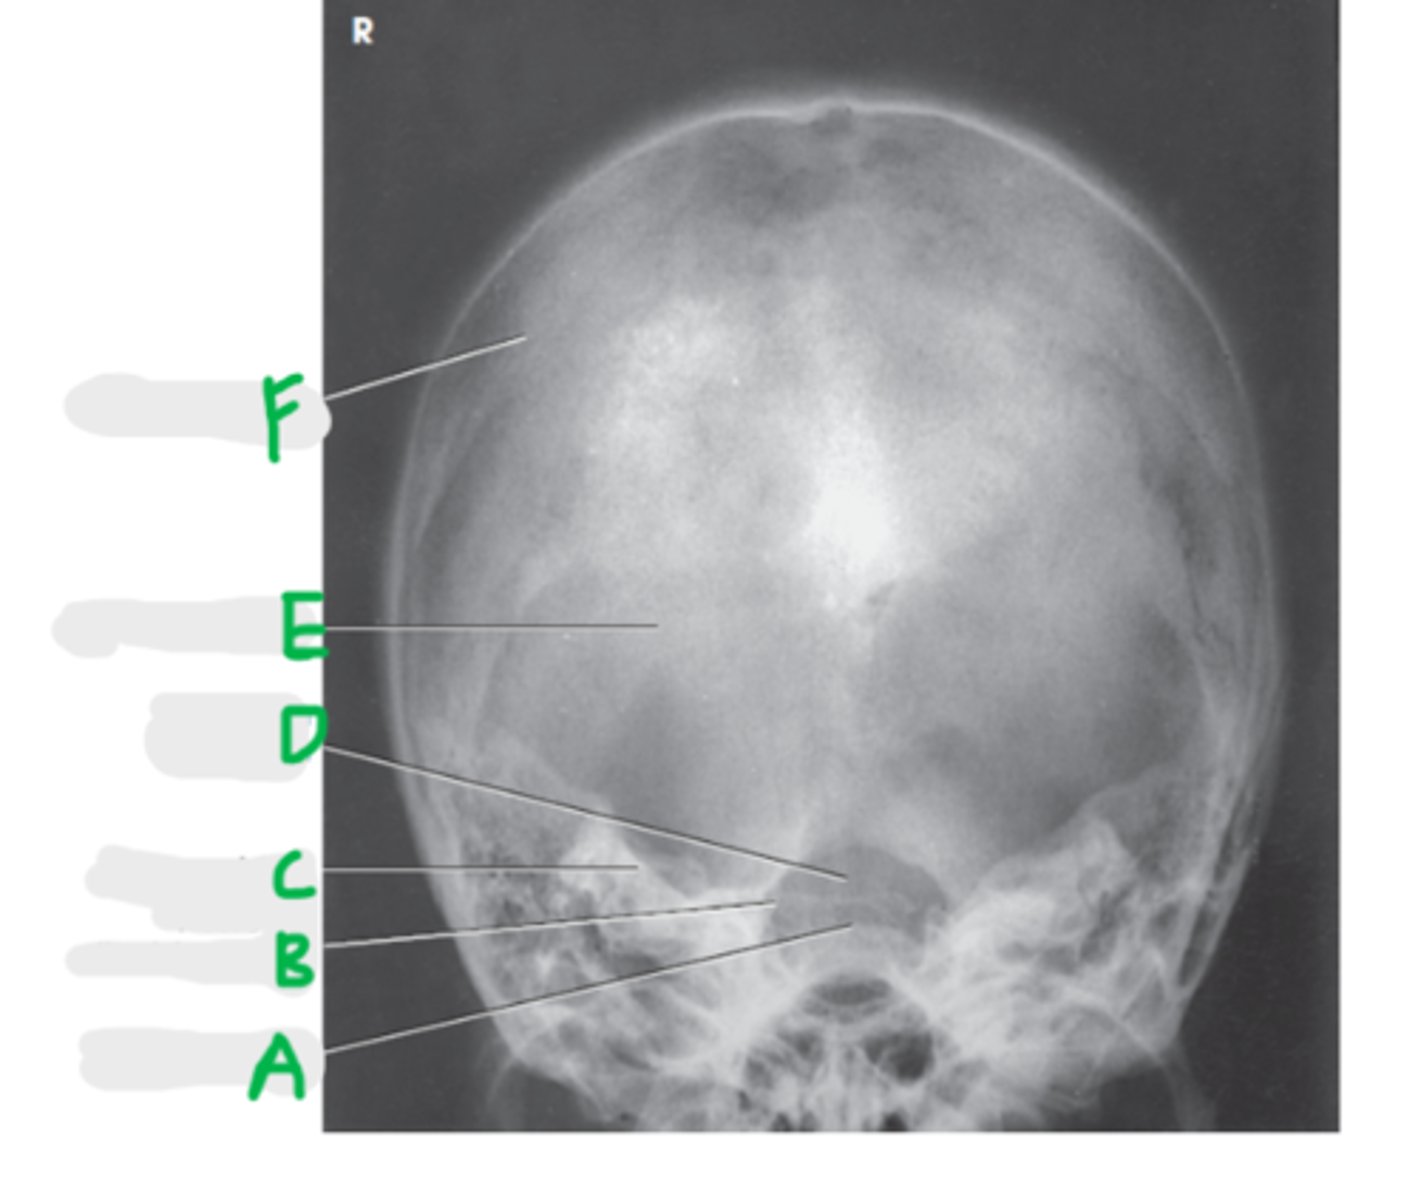

Parietal bone

A

Frontal bone

B

Dorsum sella

C

Supraorbital margin

D

Petrous ridge

E

Crista galli

F

Ethmoidal sinus

G

PA Skull

What projection is this?

Orbits fill the petrous ridges

How can we tell this is a PA skull?

CR to exit the nasion

What is the CR for a PA or PA axial (Caldwell) skull?

OML perpendicular to IR

What line should be perpendicular to the IR for a PA or PA axial (Caldwell) skull?